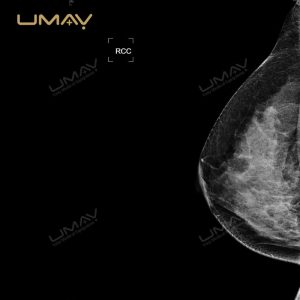

Sistema de mamografía digital para el examen de enfermedades de los senos con tecnología DR

El sistema de mamografía digital con tecnología DR está diseñado para ofrecer imágenes de alta resolución que permiten una detección temprana y precisa de enfermedades mamarias. Gracias a su avanzada tecnología de radiografía digital, este mamógrafo proporciona imágenes claras y detalladas, facilitando diagnósticos confiables tanto en evaluaciones de rutina como en estudios especializados. Su detector de panel plano optimiza la calidad de imagen, reduce el ruido y mejora la visualización de estructuras internas complejas.

Además, el sistema está diseñado para minimizar la exposición a la radiación, garantizando la seguridad de las pacientes sin comprometer la calidad diagnóstica. Su flujo de trabajo eficiente y su interfaz intuitiva lo convierten en una herramienta ideal para hospitales, clínicas y centros de imagenología dedicados a la salud de la mujer. Este equipo de última generación permite a los profesionales obtener resultados rápidos y precisos, mejorando la experiencia del paciente y elevando los estándares de diagnóstico en mamografía.